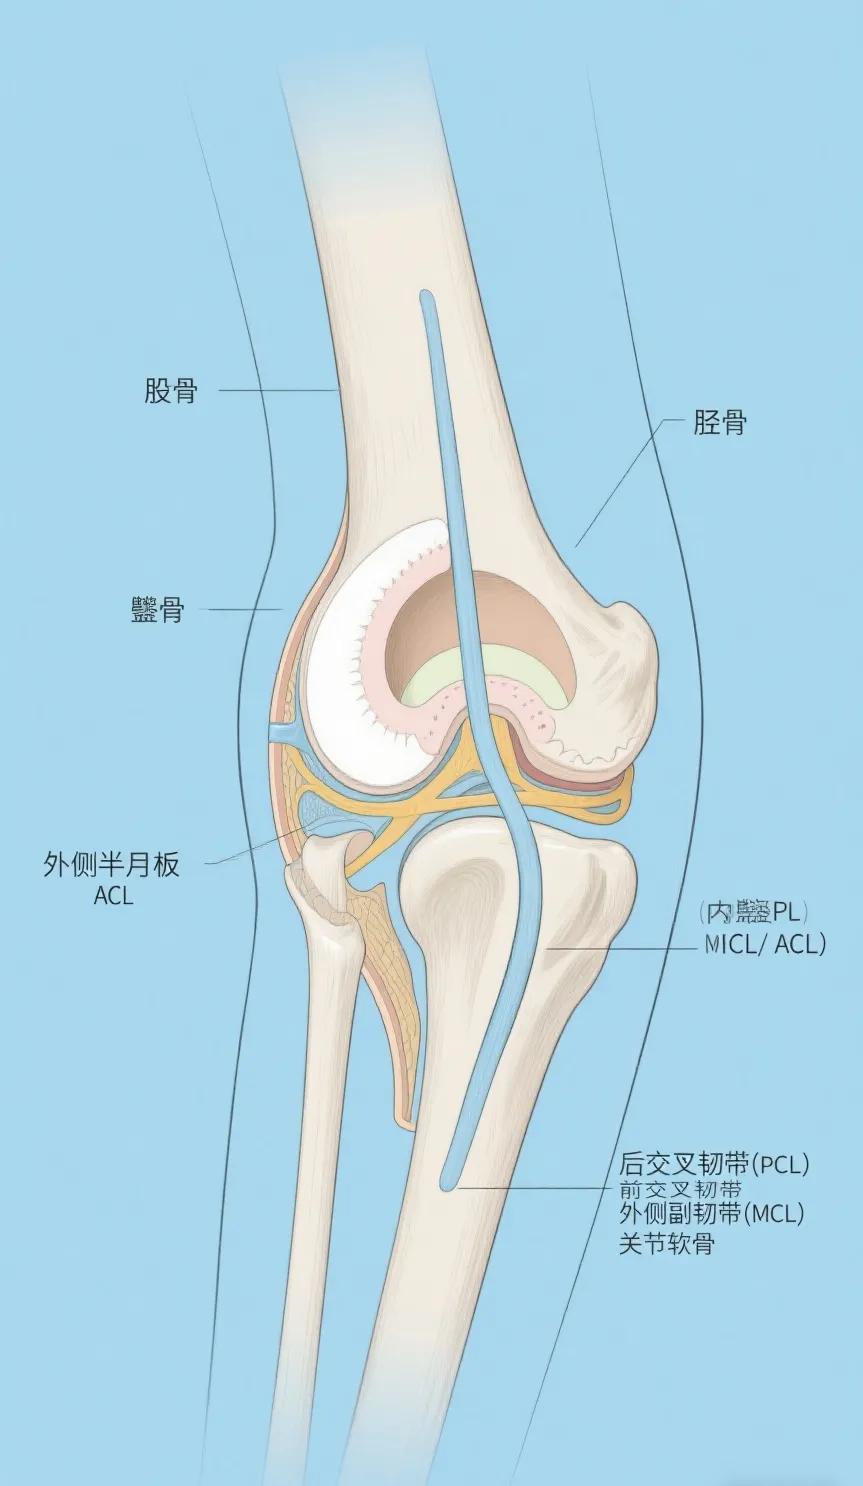

膝关节为什么会痛? 膝关节是人体最大、最复杂的承重关节,日常行走、跑跳都依赖它的稳定性和灵活性。膝关节出现疼痛,往往与自身结构损伤、过度使用或个人生活习惯密切相关。 一、膝关节的结构特点:复杂且易损伤 膝关节由骨骼、软骨、韧带、肌腱和滑膜共同组成,任何一部分受损都可能引发疼痛: 1. 骨骼与软骨:股骨、胫骨和髌骨构成关节,表面覆盖软骨,缓冲压力。软骨磨损(如退行性关节炎)会导致骨头直接摩擦,产生疼痛。 2. 韧带:内外侧副韧带和前/后交叉韧带维持关节稳定。韧带撕裂(如运动中的急停变向)会引发急性肿痛和关节不稳。 3. 半月板:膝关节内的“减震垫”,扭转动作(如深蹲时膝盖内扣)可能导致半月板撕裂,表现为关节卡压感或活动时剧痛。 4. 滑膜与滑囊:滑膜分泌润滑液,炎症(如滑膜炎)会导致关节积液、肿胀和隐痛。 关键点:膝关节结构精密,但耐冲击能力有限,长期磨损或瞬间暴力都可能导致损伤。 二、损伤机制:急性创伤与慢性磨损 膝关节疼痛通常分为两类: 1. 急性损伤 - 运动创伤:足球、篮球等运动中韧带撕裂(如ACL损伤)、半月板破裂,多因突然扭转或外力撞击。 - 意外受伤:跌倒时髌骨骨折或韧带拉伤,疼痛剧烈且伴随肿胀。 2. 慢性劳损 - 骨关节炎:中老年人常见,软骨逐渐退化,表现为晨僵、活动后疼痛。 - 髌腱炎(跳跃膝):频繁跑跳导致髌腱过度负荷,膝盖下方压痛。 - 不良姿势:长期久坐、跷二郎腿等会加重关节压力,引发慢性疼痛。 案例:长期跑步者若忽略肌肉力量训练,可能因股四头肌无力导致髌骨轨迹异常,加速软骨磨损。 三、个人原因:生活习惯与风险因素 除了结构问题,个人因素也是膝关节疼痛的重要诱因: 1. 体重超标:体重每增加1kg,膝关节负重增加3-4kg,肥胖者更易患骨关节炎。 2. 肌肉失衡:大腿前后肌群力量不均(如久坐人群腘绳肌紧张)会改变关节受力分布。 3. 运动方式错误:如健身时深蹲膝盖内扣、跑步时步幅过大,均会增加损伤风险。 4. 年龄与性别:女性激素水平变化更易出现骨质疏松和韧带松弛;老年人关节退变不可避免,但可通过锻炼延缓。